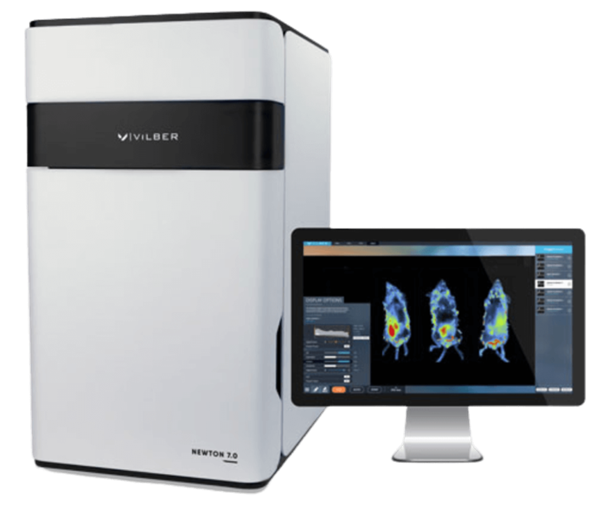

The Newton 7.0 is a state-of-the-art optical imaging system that utilizes bioluminescence, fluorescence, and 3D tomographic imaging in one device. Thanks to its sophisticated features and easy-to-use interface, it is perfect for in vitro, ex vivo, and in vivo imaging applications and for imaging numerous specimens at once.

The system has a cutting-edge 4.6-megapixel CCD camera with one of the biggest apertures. This camera's exceptional sensitivity for a range of luciferase enzymes and fluorophores frequently utilized in preclinical research makes fast and effective signal acquisition possible.

Time is saved in longitudinal studies thanks to the user-friendly software and straightforward workflow, which are geared for multi-user use.

Image Credit: Scintica Instrumentation Inc

With the user in mind, the Newton 7.0 is a cutting-edge optical bioluminescence, fluorescence, and 3D tomographic imaging system.